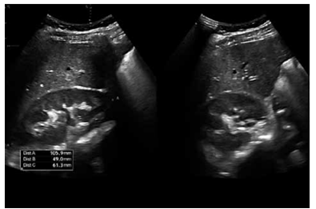

Ultrassonografia renal: rins de tamanho normal, sem alterações estruturais significativas.

(Arquivo pessoal; imagem usada com autorização)

Ultrassonografia renal: rins de tamanho normal, sem alterações estruturais significativas.

(Arquivo pessoal; imagem usada com autorização)